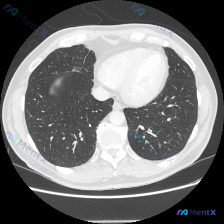

分享一个胸部CT病例,整理了思路,供大家讨论: 病例资料 - 主诉:无明确症状(偶然发现) - 现病史:无症状,体检或偶然检查发现 - 影像检查:胸部CT肺窗横断面,右肺中叶近心缘处见局灶性磨玻璃密度影(GGO),边界模糊,内部密度均匀,未见明显实变或支气管充气征;左肺及右肺其余部分正常 - 其他阳...